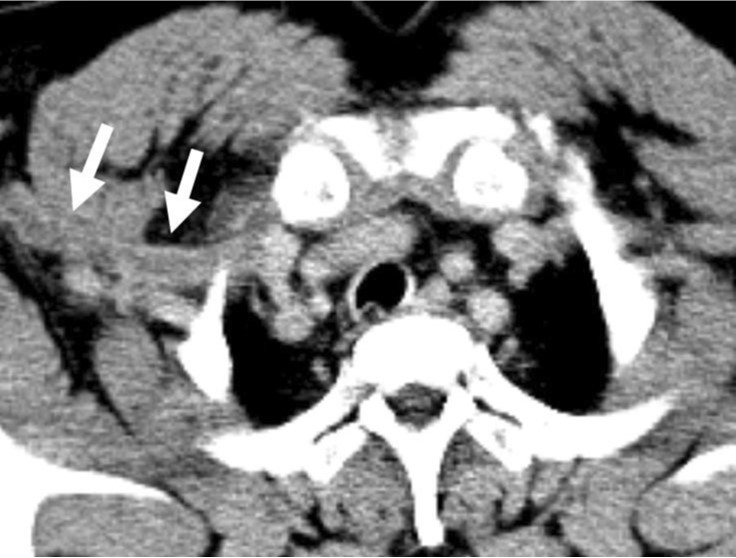

조영증강 CT에서 우측 쇄골하정 맥을 포함한 상지 심부정맥이 확장되어 있고 내부에는 혈전이 있었다(Fig. 1A-C). 우측 사각근간 삼각(interscalene triangle)에 의해 우측 쇄골하정맥이 명확하게 눌려진 소견은 없으며 우측늑쇄공간(costoclavicular space)도 좁아지거나 주변 구조물에 의해 눌려진 소견은 보이지 않아 반복적 인 작업에 의해 정맥이 눌린 노력혈전증( effort thrombosis)으로 생각하였다.

Fig. 1. A-C

Multiplan ar reconstructed images (A-C) shows contrast filling dtfecte (arrows) within right subclavian van.